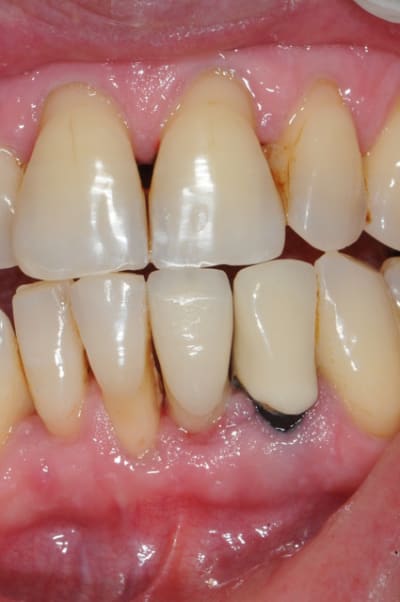

et ici ?? vous feriez quoi ?

32 et 42 pas mobiles

malheureusement, l'espace est réduit pour mettre deux implants.

comment avez vous déjà géré ce type de cas ??

le haut est déjà traité...